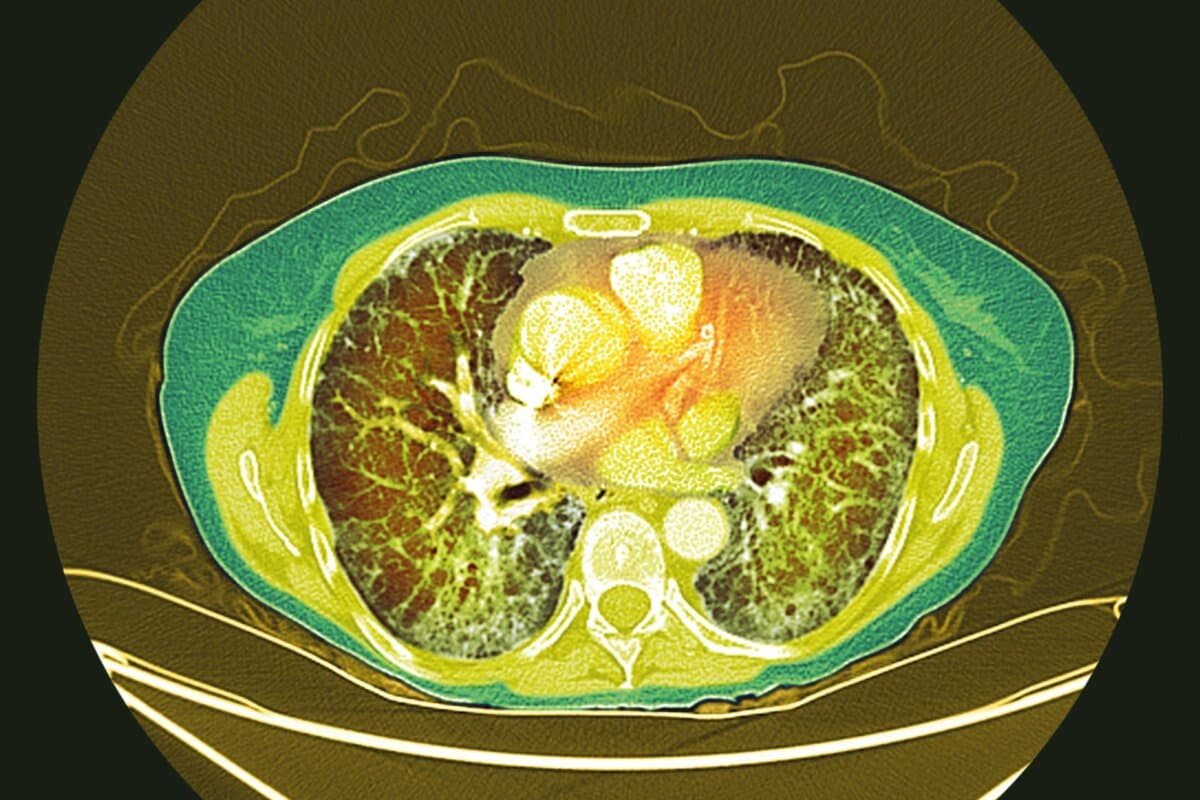

Ein wichtiges Merkmal des Studiendesigns war, dass 44 % der Teilnehmer bereits eine Therapie mit Nintedanib erhielten. Ziel der Studie war es unter anderem, zu untersuchen, ob Nerandomilast additiv zur bestehenden Therapie wirkt. Die Randomisierung erfolgte stratifiziert nach Nintedanib-Vortherapie (ja oder nein) und nach dem in der High-Resolution-CT erkennbaren fibrotischen Muster («Usual Interstitial Pneumonia»-ähnliches Muster oder nicht-UIP-Muster).